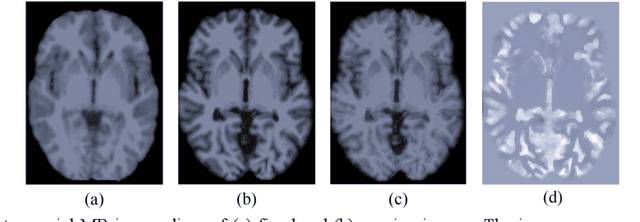

Abstract:Deformable image registration is fundamental for many medical image analyses. A key obstacle for accurate image registration is the variations in image appearance. Recently, deep learning-based registration methods (DLRs), using deep neural networks, have computational efficiency that is several orders of magnitude greater than traditional optimization-based registration methods (ORs). A major drawback, however, of DLRs is a disregard for the target-pair-specific optimization that is inherent in ORs and instead they rely on a globally optimized network that is trained with a set of training samples to achieve faster registration. Thus, DLRs inherently have degraded ability to adapt to appearance variations and perform poorly, compared to ORs, when image pairs (fixed/moving images) have large differences in appearance. Hence, we propose an Appearance Adjustment Network (AAN) where we leverage anatomy edges, through an anatomy-constrained loss function, to generate an anatomy-preserving appearance transformation. We designed the AAN so that it can be readily inserted into a wide range of DLRs, to reduce the appearance differences between the fixed and moving images. Our AAN and DLR's network can be trained cooperatively in an unsupervised and end-to-end manner. We evaluated our AAN with two widely used DLRs - Voxelmorph (VM) and FAst IMage registration (FAIM) - on three public 3D brain magnetic resonance (MR) image datasets - IBSR18, Mindboggle101, and LPBA40. The results show that DLRs, using the AAN, improved performance and achieved higher results than state-of-the-art ORs.